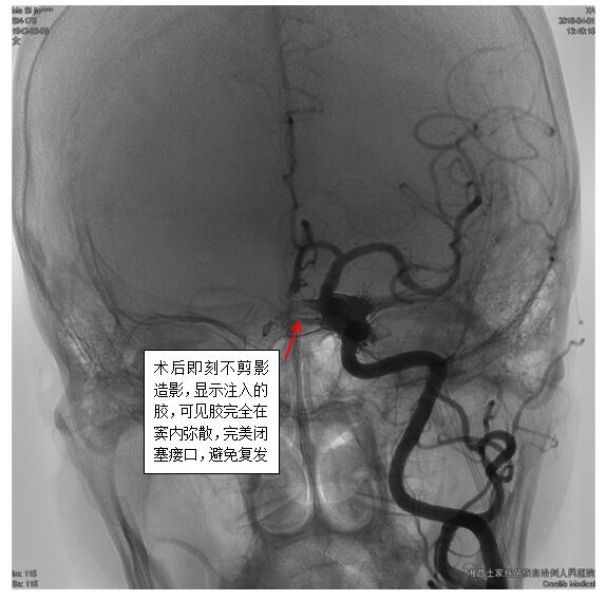

最终,经过充分准备,凭借精湛的技术,手术组田勇副主任医师、梁承财主治医师在刘凡教授指导下,在护理人员及麻醉师同力合作下,顺利通过颈内静脉-岩下窦入路,采用弹簧圈辅助加注入onxy胶的方式完全闭塞瘘口,患者术后没有神经功能缺损。

硬脑膜动静脉瘘(DAVFs)临床较少见,它是海绵窦、侧窦、矢状窦等硬膜窦及其附近动静脉间的异常交通,为颅内外供血动脉与颅内静脉窦沟通,多见于成年人,其供血动脉为颈内动脉、颈外动脉或椎动脉的脑膜支,血液分流入静脉窦。由于动脉血液直接流入静脉窦而导致静脉窦内血液动脉化及静脉窦内压力增高,从而使得脑静脉回流障碍甚至逆流,出现脑水肿、颅内压增高、脑代谢障碍、血管破裂出血等病理改变。该病人正是由于海绵窦区的DAVFs,向海绵窦区静脉引流,导致左侧海绵窦压力增高,出现左侧动眼神经麻痹的症状。对于该病,首选经静脉入路的瘘口胶栓塞。但该病不仅少见,而且由于DAVFs的结构复杂性,以及病变周围有许多重要的组织结构,如果靶点没有完全栓塞,很容易复发,如果不慎栓塞了正常结构,有可能出现神经功能损害,加上栓塞胶的弥散相对难把握性,所以DAVFs的治疗被誉为神经介入治疗的皇冠上的宝石,具有很大的挑战性。该病人瘘口引流量比较大,如果不及时闭塞瘘口,不仅动眼神经麻痹无法恢复,而且随着瘘口进一步扩大,如果出现皮层静脉的引流后,将可能使病变更加复杂,并可能出现严重的颅内出血。